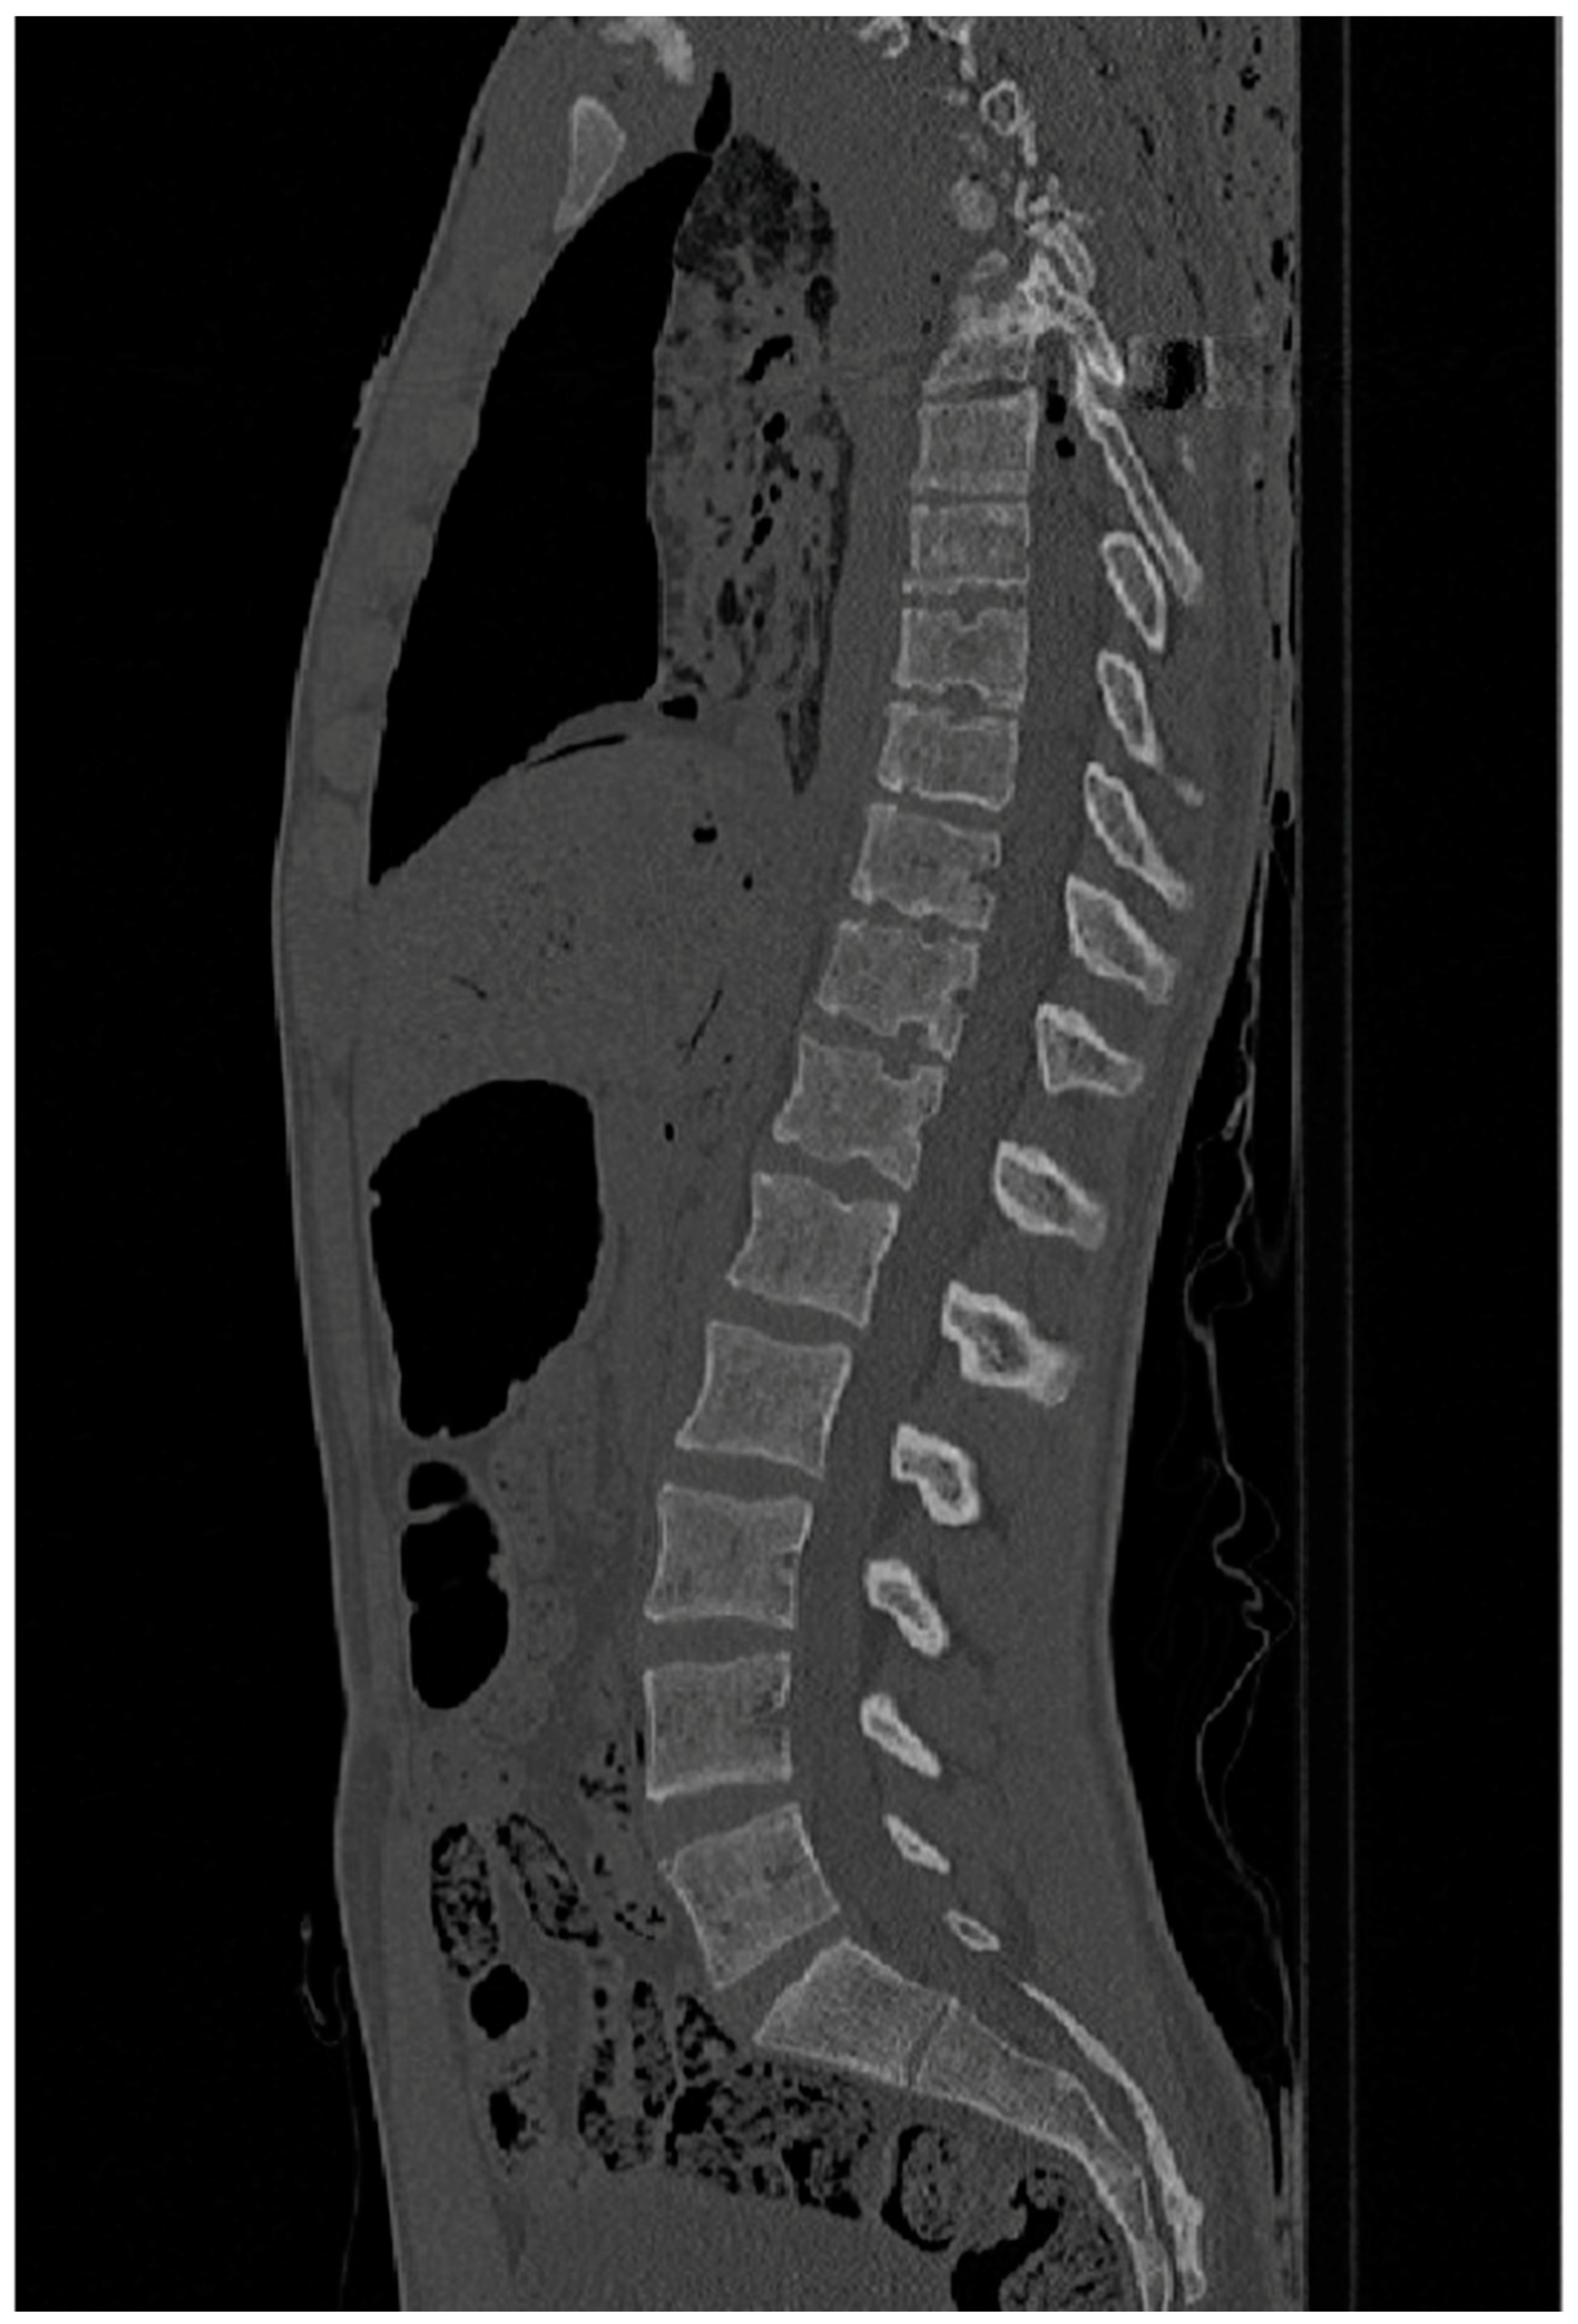

The CT scans were provided by the New Mexico Decedent Image Database; therefore, no CT imaging equipment was needed in this research to gather the images. The machine used by the researchers from the NMDID to perform the scans was a Phillips Brilliance Big Bore with a Radiation Therapy flat carbon fibre top, producing images like the ones shown in Figure 2 and Figure 3.

Figure 2.

CT slice from ID 105469 showing Schmorl’s nodes between L1 and T7, manifestig as cirular deviations into adjacent vertebrae. Reprinted with permission from [16].

To identify the presence of any Schmorl’s nodes, Thermo Fisher Scientific’s Avizo Lite software was used to set the CT scans in different planes to allow for the visualization of the layers. Three-dimensional models were then also constructed from the scans to provide a detailed image. Along with the segmentation images, this was used to identify any Schmorl’s nodes in the individuals (Figure 2 and Figure 3).